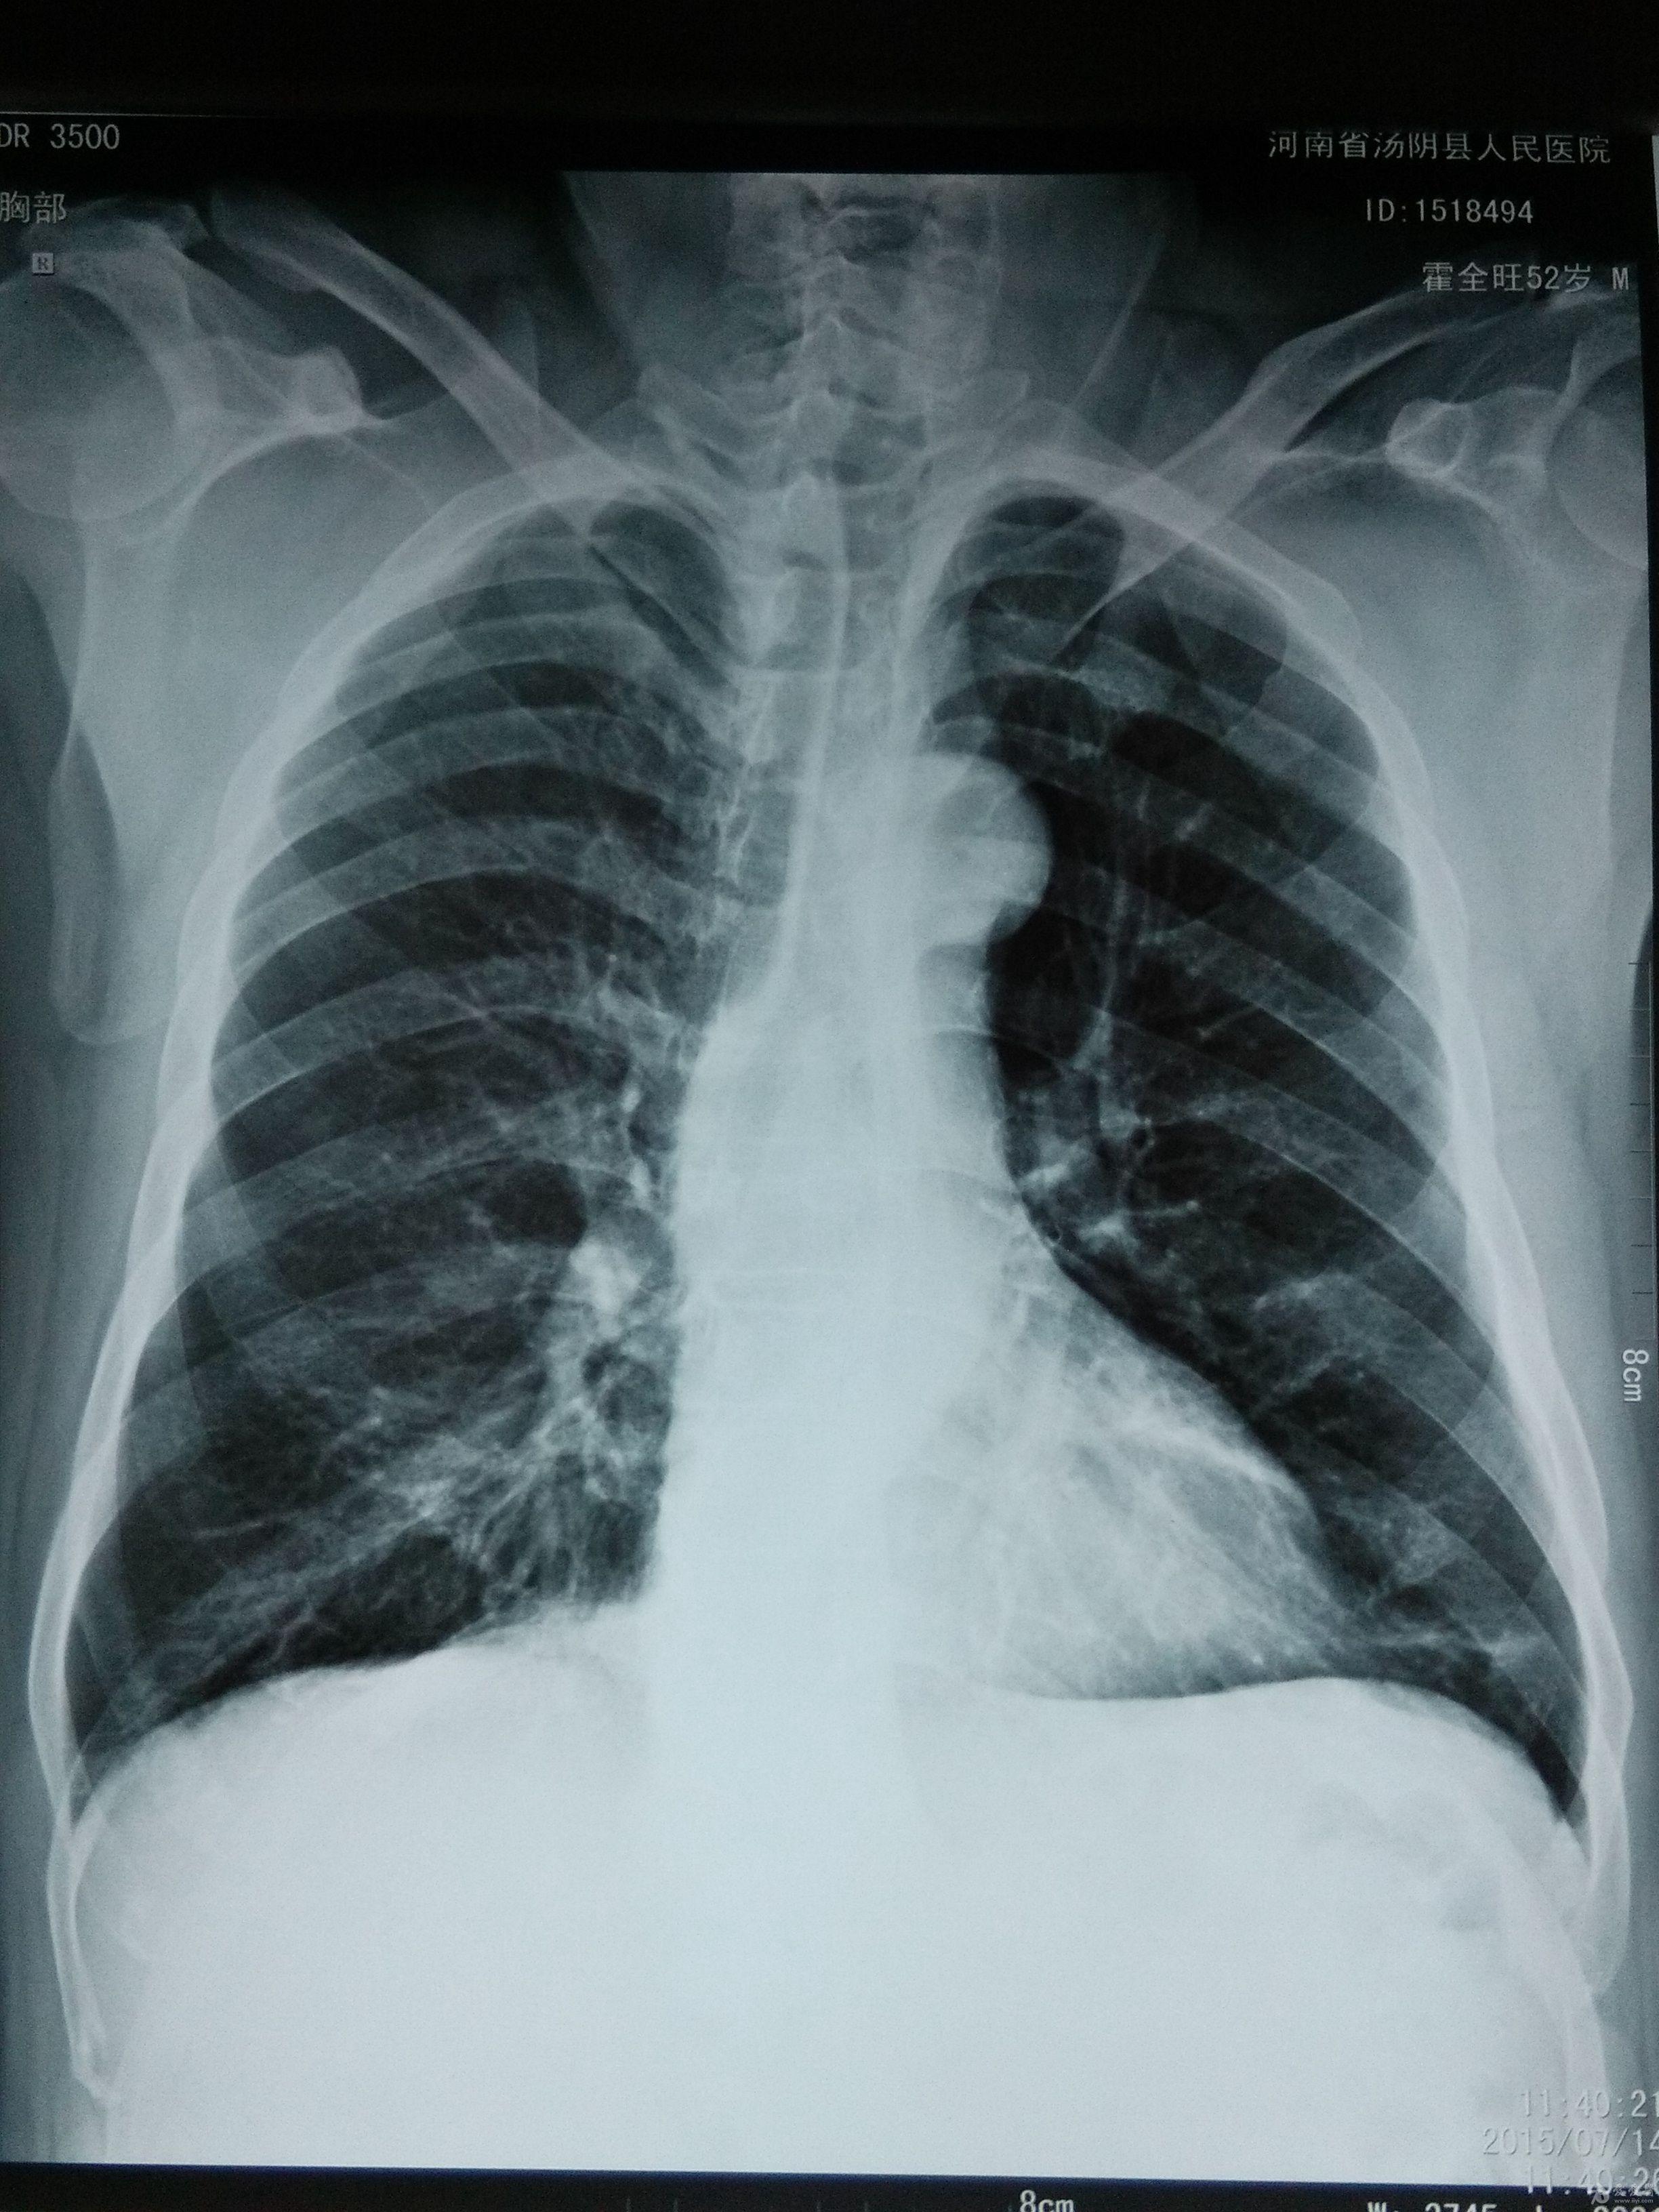

第 9 肋骨 骨折-肋骨の全体的な骨折では前述した通り第4肋骨~第8肋骨の骨折が多くなります。 しかし、ゴルフや野球のスイングなどによる疲労骨折のケースでは第4肋骨~第8肋骨だけでなく 第1肋骨 第2肋骨 の2箇所も疲労骨折を生じやすくなります。 一、第九根肋骨骨折是否严重 肋骨骨折容易并发以下的疾病,还是比较严重的: 1急性心力衰竭 肋骨骨折并发急性心力衰竭的病例多为多发性肋骨骨折,此病的患者早期应密切观察生命体征及病情变化,防止心肺功能衰竭,一旦出现早期症状应立即组织抢救,严防发生心跳骤停,心跳一旦停止不

症状: 休克 胸痛 无力 水肿 表现: 1、症状 偶尔由于剧烈的咳嗽 或喷嚏等,胸部肌肉突然强力收缩而引起肋骨骨折,称为自发性肋骨骨折,多发生在腋窝部的第6~9肋,当肋骨本身有病变时,如原发性肿瘤或转移瘤等,在很轻的外力或没有外力作用下亦可发生肋骨骨折,称为病理性肋骨骨折。我想问一下肋骨折了一根然后 如果肋骨折了插到肺里去会有生命危险吗? 本人今年51岁,四个月前上肋骨折接好后, 肋骨折后如何睡觉 ;